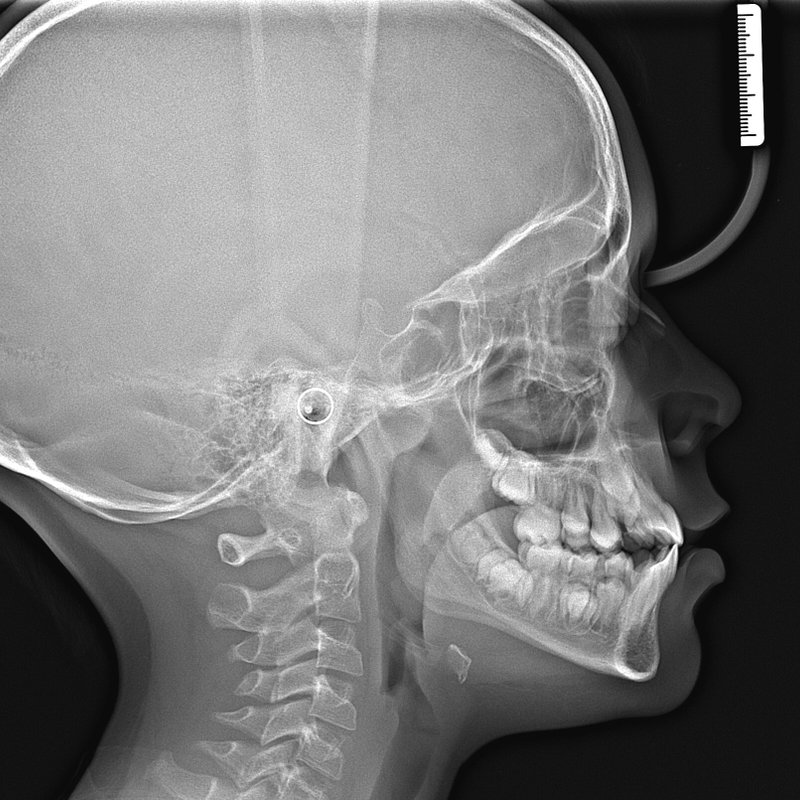

Фотографии и схемы для ОПТГ и мезиального прикуса